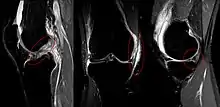

The unhappy triad, also known as a blown knee among other names, is an injury to the anterior cruciate ligament, medial collateral ligament, and meniscus. Analysis during the 1990s indicated that this 'classic' O'Donoghue triad is actually an unusual clinical entity among athletes with knee injuries. Some authors mistakenly believe that in this type of injury, "combined anterior cruciate and medial collateral ligament (ACL- MCL) disruptions that were incurred during athletic endeavors" always present with concomitant medial meniscus injury. However, the 1990 analysis showed that lateral meniscus tears are more common than medial meniscus tears in conjunction with sprains of the ACL.[1]

The unhappy triad occurs due to a lateral blow to the knee causing a rupture in the anterior cruciate ligament, medial collateral ligament, and meniscus. Injury is most often sustained when a lateral (from the outside) force impacts the knee while the foot is fixed on the ground. The strong valgus or rotary force to the knee tears the ACL, MCL, and medial meniscus all together. This type of injury occurs often in contact sports such as football, rugby, or motocross. During the injury, the leg is laterally rotated and over-abducted. In about 10% of cases, the force is applied to the opposite side of the knee, and the lateral and posterolateral ligaments are torn.

Injury

Injury

The tear of meniscus is among the most common knee injuries. It is usually caused by torsional stress; twisting or turning of the knee too quickly with the foot planted on the ground while the knee is flexed. The feeling of a "pop" in the knee is usually felt when the meniscus is torn. Athletes, particularly those who participate in contact sports, are at a greater risk for meniscal tears. Sports-related meniscal tears often occur with other knee injuries, such as an anterior cruciate ligament tear.

Because the medial collateral ligament resists widening of the inside of the knee joint, the ligament is usually injured when the outside of the knee joint is struck. This force causes the outside of the knee to buckle, and the inside to widen. When the MCL is stretched too far, it is susceptible to tearing and injury. This is the injury seen by the action of "clipping" in a football game.

An injury to the MCL may occur as an isolated injury, or it may be part of a complex injury to the knee. Other ligaments ACL, or meniscus, may be torn along with a MCL injury.